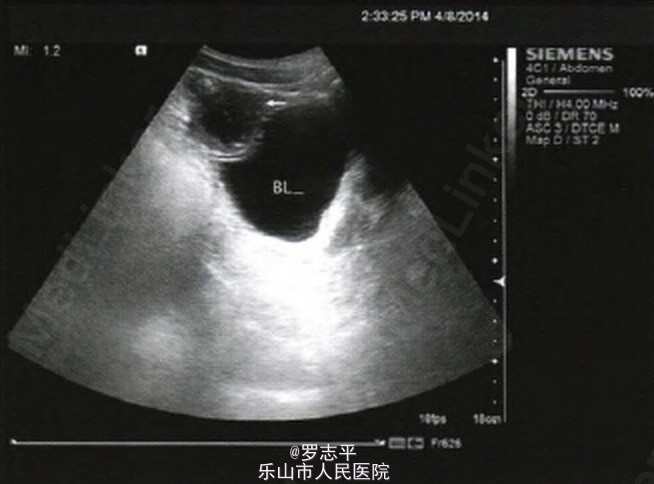

看到一例和交叉普外科和泌尿外科的病例,本来在很多医院这两个科室也是不分的,所以PO在这里给大家分享下。 患者,男,22岁。病史:腹腔镜下阑尾切除术后2年余,阑尾病检结果提示:阑尾坏疽。术后腹部切口反复感染1年余,经加强切口换药后,腹部切口愈合。现已康复半年余。20天前出现尿频、尿急、尿痛就诊于我院。入院后膀胱超声提示:膀胱前壁低回声,性质待定(图1)。CT检查提示:膀胱顶部占位;膀胱癌?(图2)。门诊膀胱镜检查发现膀胱顶部3 cm×3 cm×3 cm大小类圆形占位,表面滤泡样改变,基底部较广。取病理活检提示:(膀胱顶部)送检少许破碎组织显示尿路上皮增生(送检组织较少)。 患者入院后于2014年4月15日在全麻下行经尿道膀胱占位活检术。术中冷冻活检结果提示:慢性膀胱炎。故改行膀胱部分切除术,术中见肿物位于膀胱顶部,膀胱外腹膜质地硬,呈增殖样改变,盆腔内大网膜、肠壁及腹膜相互粘连严重。将肿物及局部腹膜一并切除。术后病检结果提示:(膀胱)慢性肉芽肿性炎伴微脓肿形成。